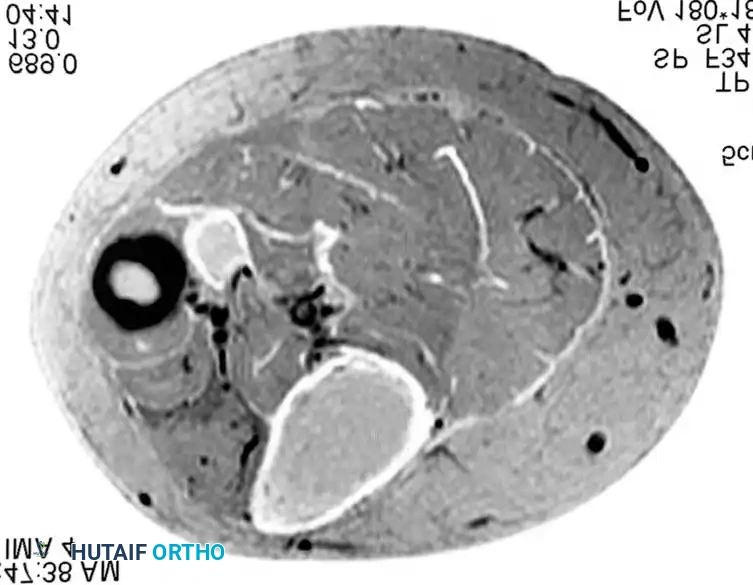

BENIGN TUMORS AND TUMOR-LIKE LESIONS Surgical Diagram

MRI and intraoperative excision of an intramuscular hemangioma. Note the serpiginous vascular channels and interspersed adipose tissue.